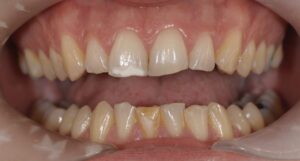

Le congrès de l’EAPD (Académie Européenne d’Odontologie Pédiatrique) a défini des critères de diagnostic en 2003. A savoir des opacités délimités, des fractures post-éruptives, des restaurations atypiques ainsi que que des extractions des molaires. (3) Le diagnostic différentiel doit surtout s’établir entre des amélogénèses imparfaites et des hypominéralisations d’origine traumatique pour les dents antérieures. Cliniquement, les dents vont présenter des colorations blanches ou brunes opaques sur une partie ou sur toute la surface de la dent (Figures 1-2-3-4).

Cette atteinte peut être soit légère (émail blanc, opaque), soit modérée (coloration jaune, brune, surface crayeuse et effondrement postéruptif de l’email ou PEB) ou enfin sévère (atteintes associées à des pertes de substances importantes). De plus, l’intégrité de la dent peut être aussi touchée. Plus la MIH est sévère et plus le manque d’émail sera important donc plus les sensibilités/douleurs seront importantes aussi. Cette sévérité varie en fonction des personnes, mais également au sein des dents d’un même individu : on parle d’atteinte asymétrique. Toutes les dents ne sont pas toutes touchées de la même façon, et ne nécessiteront donc, pas les mêmes types de soin.

Les patients ayant cette pathologie présentent des hypersensibilité importantes entrainant en plus des difficultés d’anesthésie. Au préjudice esthétique antérieur s’ajoute un risque carieux plus élevé ainsi que des échecs thérapeutiques (adhésion, fracture…). Cela engendre une anxiété majorée chez ses patients qui ont 10 fois plus de soins que la moyenne. Pour toutes ces raisons, cette pathologie est considérée comme un problème de santé publique par de nombreux pays. Les thérapeutiques sont principalement tournées vers la prévention et un suivi rigoureux afin de mettre en place les solutions adaptées au moment opportun. En fonction de la sévérité, cela allant de simples protocoles de fluorations jusqu’à l’extraction des dents concernées. Le dépistage est donc important, lors du diagnostic d’un patient il conviendra d’examiner la fratrie ainsi que les parents.